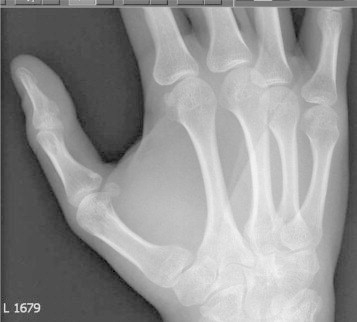

The patient was followed up in the clinic 2 weeks after the surgery. The wound had healed satisfactorily. There was complete resolution of the pre-operative pain. The patient was reviewed again in the clinic after 3 months. By then patient had made a full clinical and functional recovery. The radiograph showed that the cyst had healed completely (Fig. 4). He was discharged from the clinic. Quick DASH (Disabilities of the Arm, Shoulder and Hand) score was 23.9 at 3 months.

Fig. 4.

The radiograph at 3 months follow-up showing the lesion well healed.